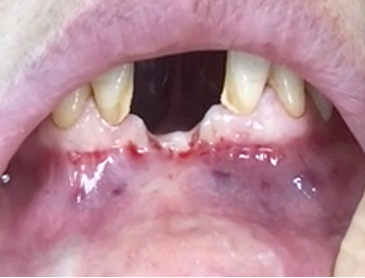

A clinical case using resorbable membrane

• A clinical case using resorbable membrane 1